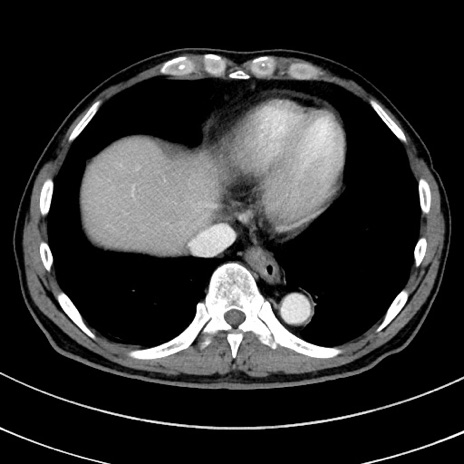

症例8(横断像)

【症例】 60歳代男性

【主訴】 黒色吐物

【現病歴】 4日前から嘔気自覚、2日前の朝食後にも嘔気あり、自分で手で嘔吐反射起こし嘔吐したところ血が混ざっていたため受診。

【既往歴】 5年前汎発性腹膜炎を伴う急性虫垂炎で手術、高血圧、前立腺肥大症、高脂血症

【身体所見】 腹部正中に手術癩痕あり 腹部平坦・軟圧痛なし膨満感あり

【データ】WBC 8400、CRP 4.54